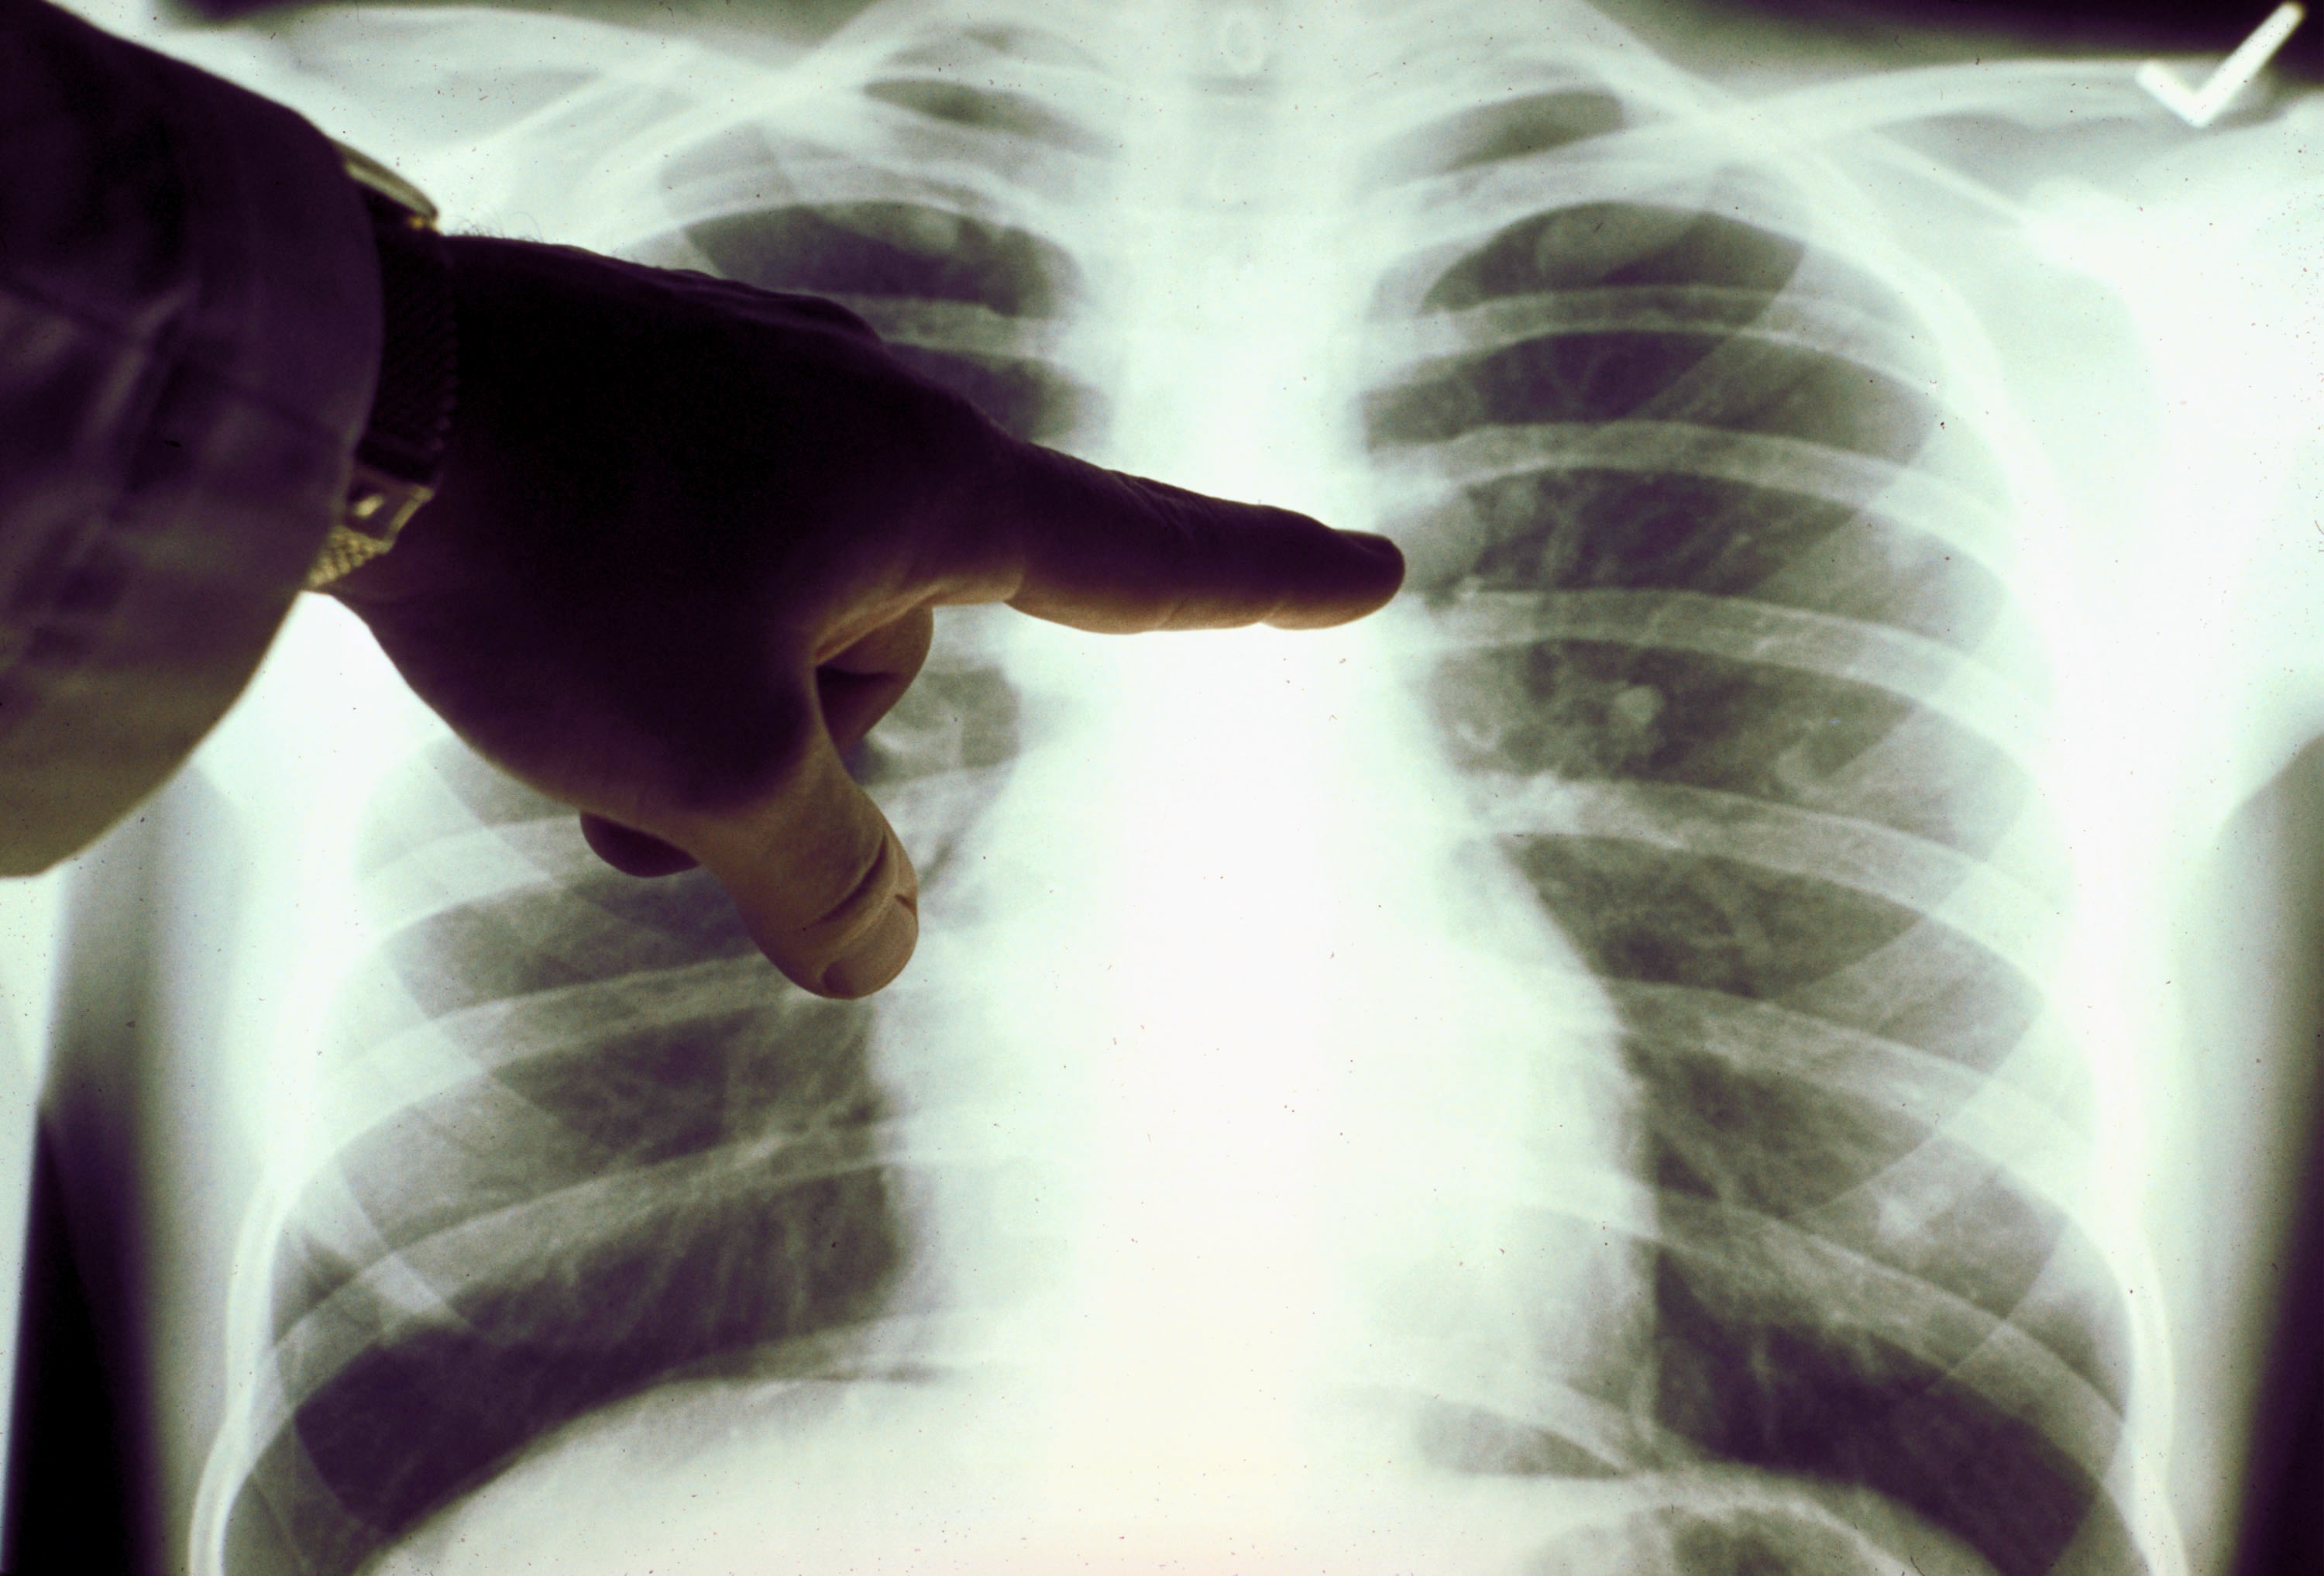

Симптомы туберкулеза: Как распознать и что делать

Раздел: Визуальные уроки